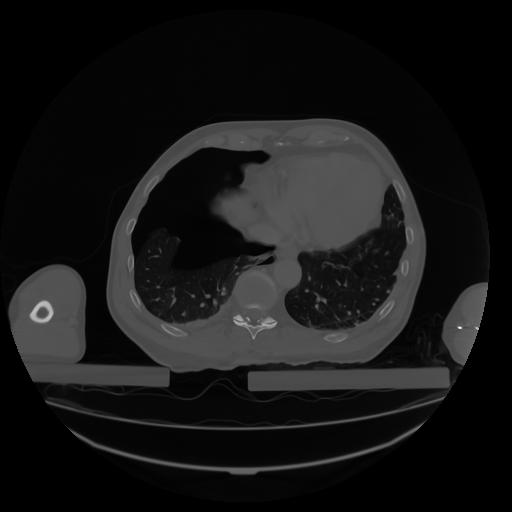

27 CUERPO,CE,Axial,3.0,CUERPO,,